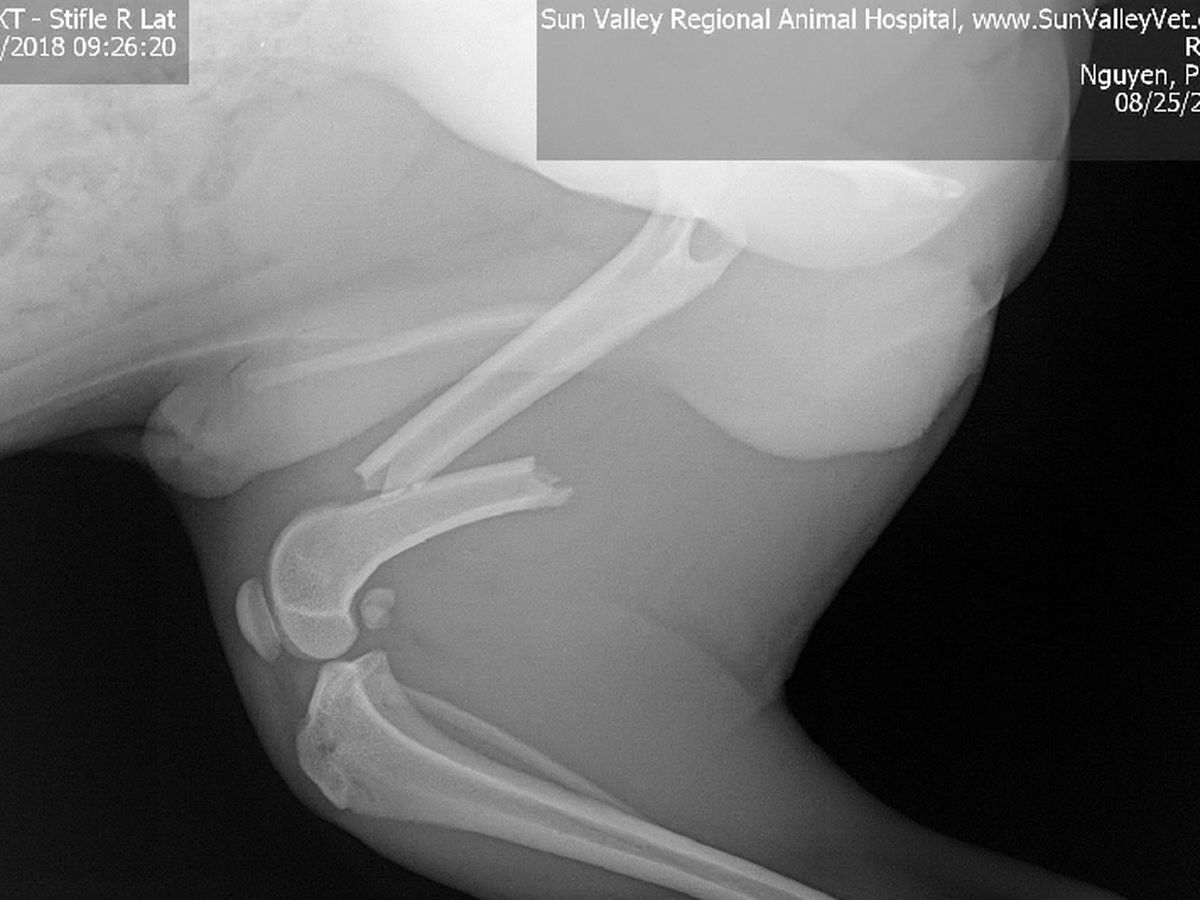

My name is Phero Peter and this is Rufio. We had a bad accident. We are still finishing up our move and Rufio had jumped onto our highest furniture and down onto my luggage that he slipped off of and broke his leg.

The money is for Rufio's orthopedic surgery. The Sun Valley Animal Hospital had attempted to do a "splint surgery" for Rufio and failed. They still gave me the bill for it but removed the cost of the attempt.

The vet said the cost will be between 2905.60 to 3641.95 so anything helps.